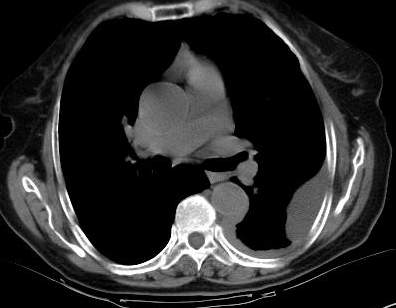

请上传纵隔窗。目前还是支技包裹性积液(明显梭形),即使是间皮瘤并积液也少梭形的。

以下是引用曼一拍在2004-8-26 20:05:47的发言:[br]请上传纵隔窗。目前还是支技包裹性积液(明显梭形),即使是间皮瘤并积液也少梭形的。

从图片看,包裹性积液好象更合理,梭形,ct值3-5hu(在哪看到的?);胸膜间皮瘤如此规则,不多见。

左侧背部胸膜肥厚,伴包裹性积液,不考虑间皮瘤.

同意以上各位的高见,首先考虑包裹性积液,1.胸膜间皮瘤积液量一般较大,以游离性积液更为常见,2.可以看到增厚的胸膜结节